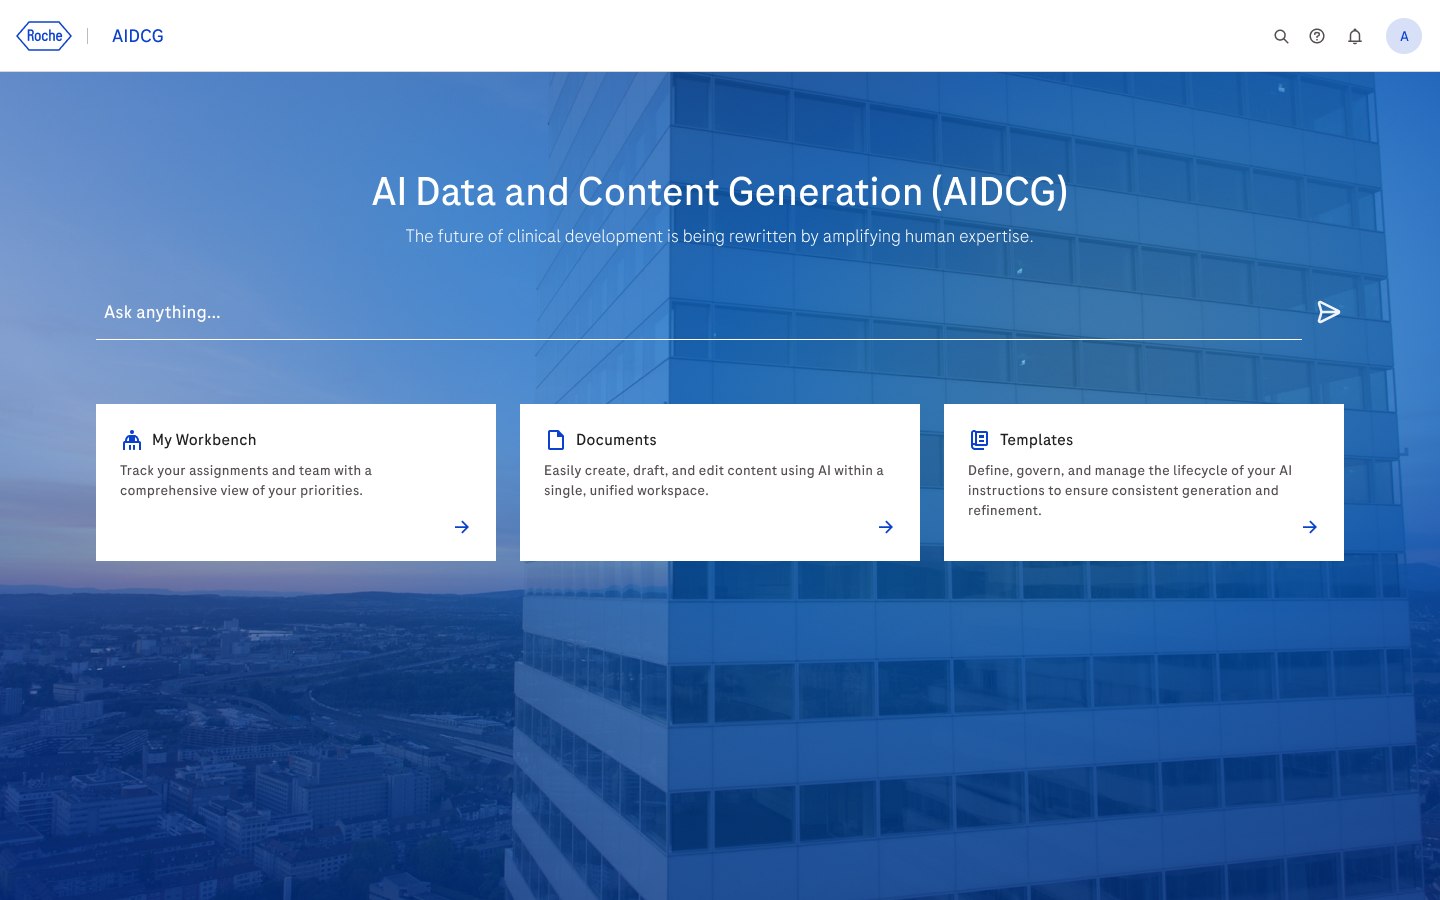

AIDCG, Roche

Managing a dedicated design team in building an AI-powered ecosystem for clinical documentation, streamlining complex workflows into a cohesive product.